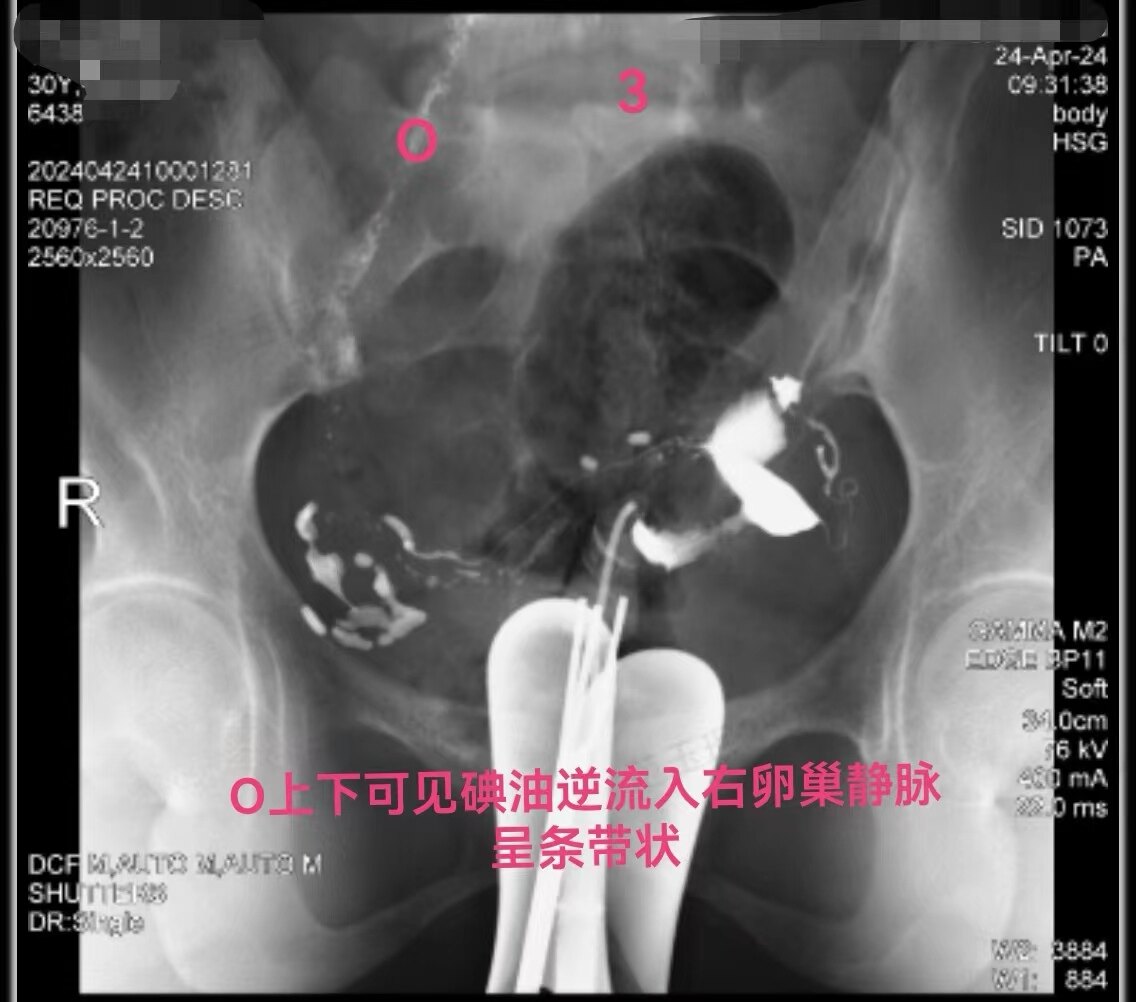

在做子宫输卵管造影检查时:当所用造影剂为碘油,出现静脉和淋巴管逆流时,立即停止造影检查是对的。因为碘油和血液不能相容混合一起,碘油会形成油栓。因此,当碘油进入静脉和淋巴管后会进入下腔静脉,进入右心房,进而进入肺动脉,形成肺栓塞,可危机被检查者生命安全。但是,当所用造影剂为碘水,出现静脉和淋巴管逆流时,可以继续造影检查,直至满足临床诊断后再结束检查。因为碘水和血液可以相容会混合一起,碘水逆流进入静脉和淋巴是安全的。大家好多做过CT增强检查,成年人一般需要用高压注射器要向静脉内快速注入100毫升碘水进行检查,都是安全的。造影注入10毫升左右碘水,即使都进入静脉也没事。这二例,一例碘油造影是一大学附属妇产医院做放射科的,该立即停止造影却没有停止。万幸,逆流进入静脉的碘油少,没有造成严重后果。另外一例碘水造影是一省妇幼保健院放射科做的,不该停止造影检查,反而停止造影检查,未能完成检查,不能给正确诊断。

第一例碘油造影图和报告单